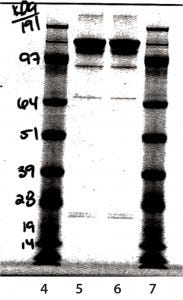

Figure 8: Nonreduced sodium-dodecyl sulfate polyacrylamide gel electrophoresis (SDS-PAGE)

Figure 9: Reduced sodium-dodecyl sulfate polyacrylamide gel electrophoresis (SDS-PAGE

SDS-PAGE Analysis: In Figure 8, lane 5 is a nonreduced sample from a glass vial. Lane 6 is a nonreduced sample from an Advasept vial. In Figure 9, lane 5 is a reduced sample from a glass vial. Lane 6 is a reduced sample from an Advasept vial. Pre- and postfill and stability SDS- PAGE data show comparable heavy- and light-chain bands for both glass and Advasept vials.